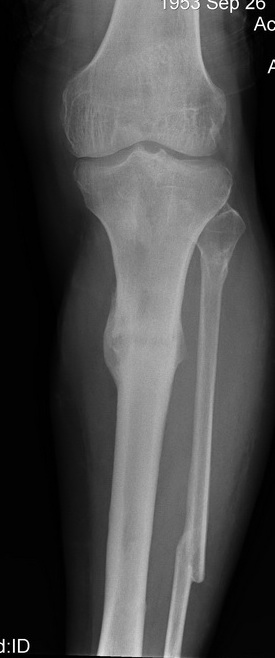

Итак - удалили стержень, воспалительный процесс к тому моменту купирован, наложили кастовую повязку и в течение 3 месяцев на контрольных рентгенограммах - признаки консолидации. Уже в сентябре, т.е черз 5 месяцев после нагноения пациент вернувшиь с подвождной охоты привез здорового сазана - основная жалоба - ноги побаливают после длительного лпаваня в ластах. Прилагаю снимки через год после удаления стержня. Вот такая, на этот раз счастливая казуистика.